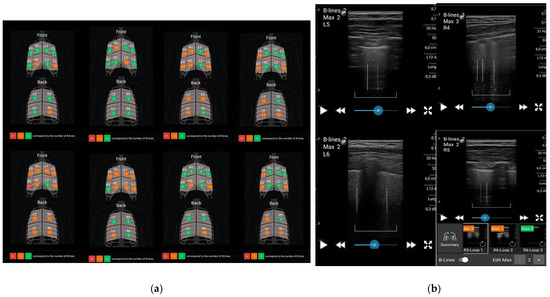

B-lines were detected in all cases, with an average of 5.42 ± 2.60 out of a maximum of 24 points across 12 regions examined, with the most common locations being the lower segments: R2, L4 (anterior), and R6 (posterior). Examples of ultrasound B-lines reports are illustrated in Figure 2. The majority of scanned regions were coded as “green”, with an average of 6.68 ± 2.61 B-lines. Regions coded as “orange” had an average of 5.21 ± 2.46 B-lines, while regions with three or more B-lines, coded as “red”, had an average of 0.10 ± 0.44.

Figure 2.

LUS imaging: scanned regions with color code assessment (a) and B-lines within lung sliding (b).

The distribution and anatomical landmarks are summarized in Table 3, with the typical scanning mode illustrated in Figure 1. B-lines in each thoracic region were counted according to the validated OMERACT definition [9]. A color-coded system was applied: “green 0” indicating no B-lines, “orange 1–2” representing 1 to 2 B-lines, and “red 3+” denoting 3 or more B-lines. A region was considered positive for ILD if there were ≥3 B-lines in a single region or >5 in adjacent spaces. Additionally, the appearance of 10 or more B-lines in a region, known as the “all-white” pattern, was noted [26]. A B-line score ranging from 0 to 24 was calculated by summing 1 point for each region with a red color code across the 12 scanned regions. Regions with green or orange color codes did not receive any points [26].